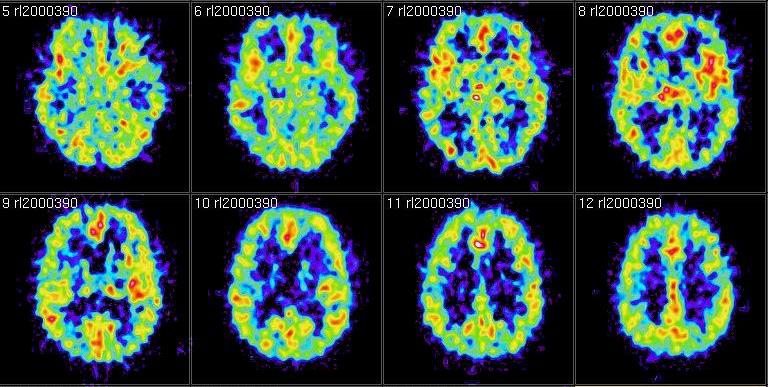

ZURIGO – Per la prima volta al mondo dei neurochirurghi svizzeri hanno effettuato un intervento al cervello con gli ultrasuoni, e pertanto senza dover aprire la scatola cranica. Lo annuncia l’Università di Zurigo, spiegando che Daniel Jeanmonod e Ernst Martin hanno applicato alla chirurgia intracranica la tecnica degli ultrasuoni focalizzati ad alta intensità, già utilizzata da anni in ginecologia e contro i tumori alla prostata.

Durante uno studio clinico, avviato nel settembre scorso, dieci adulti sono stati sottoposti all’intervento, che si è concluso con successo e senza complicazioni. Le operazioni sono state effettuate senza anestesia su pazienti totalmente coscienti e in ambulatorio.

I malati trattati soffrivano di dolori di origine neurologica, ha precisato Martin all’agenzia svizzera Ats. Una patologia che colpisce spesso le persone che hanno subito un’amputazione. Il cervello non riceve più messaggi dagli arti, i nervi inviano stimoli che danno dolori. Gli ultrasuoni – secondo gli esperti – hanno permesso di mettere a tacere questi stimoli.